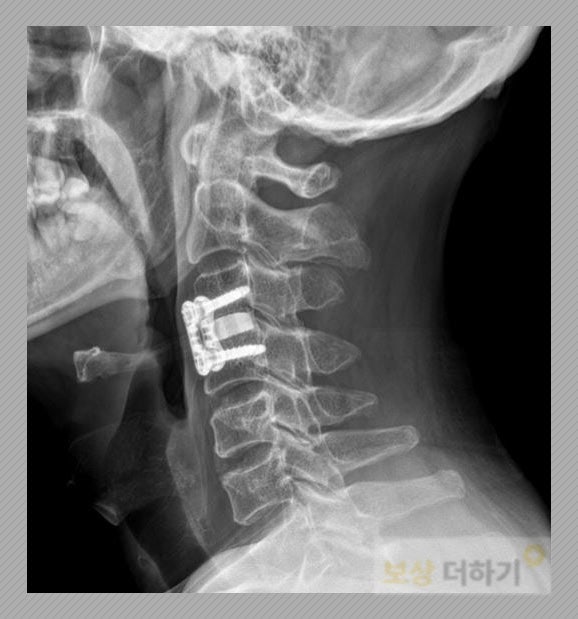

▤ 경추 3번 4번 탈구 전방 기기 고정술, 유합술

최 00 님은 유합술을 받으셨습니다. 유합술은 흔들리고 내려앉은 척추를 바로 세우고 고정시켜 안정화를 시키는 수술입니다. 보통 앞쪽에서 피부절개 후 진행하며 손상된 척추뼈 여러 개를 하나로 고정합니다. 수술명에서 알 수 있듯이 척추체를 합치는 즉 유합하는 치료방법입니다.